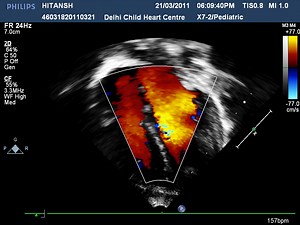

Pediatric Echo - Echo

Training - Fetal Echo

Ultrasound - Pediatrics